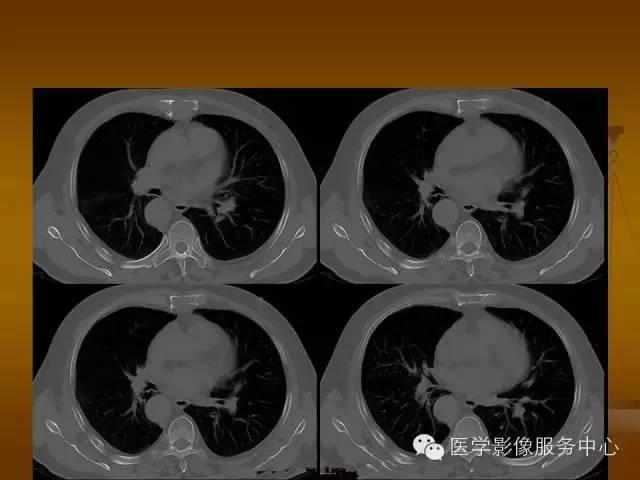

胸骨浆细胞骨髓瘤1例CT影像表现

孤立性骨髓瘤:(SBP)是由浆细胞单克隆增生导致的恶性肿瘤,是一种少见肿瘤。男性发病较女性多见。按其好发部位依次为股骨近端、椎骨、肋骨、颅骨、骨盆、锁骨和肩胛骨等,胸骨极为少见。

特征性穿凿状、鼠咬状及蜂窝状骨质破坏,边缘清楚,骨质疏松,病理性骨折及软组织肿块等表现,骨质硬化及骨膜反应少见。

骨质破坏区完全为软组织取代,骨质膨胀,边界清楚,常突破骨皮质形成软组织肿块。